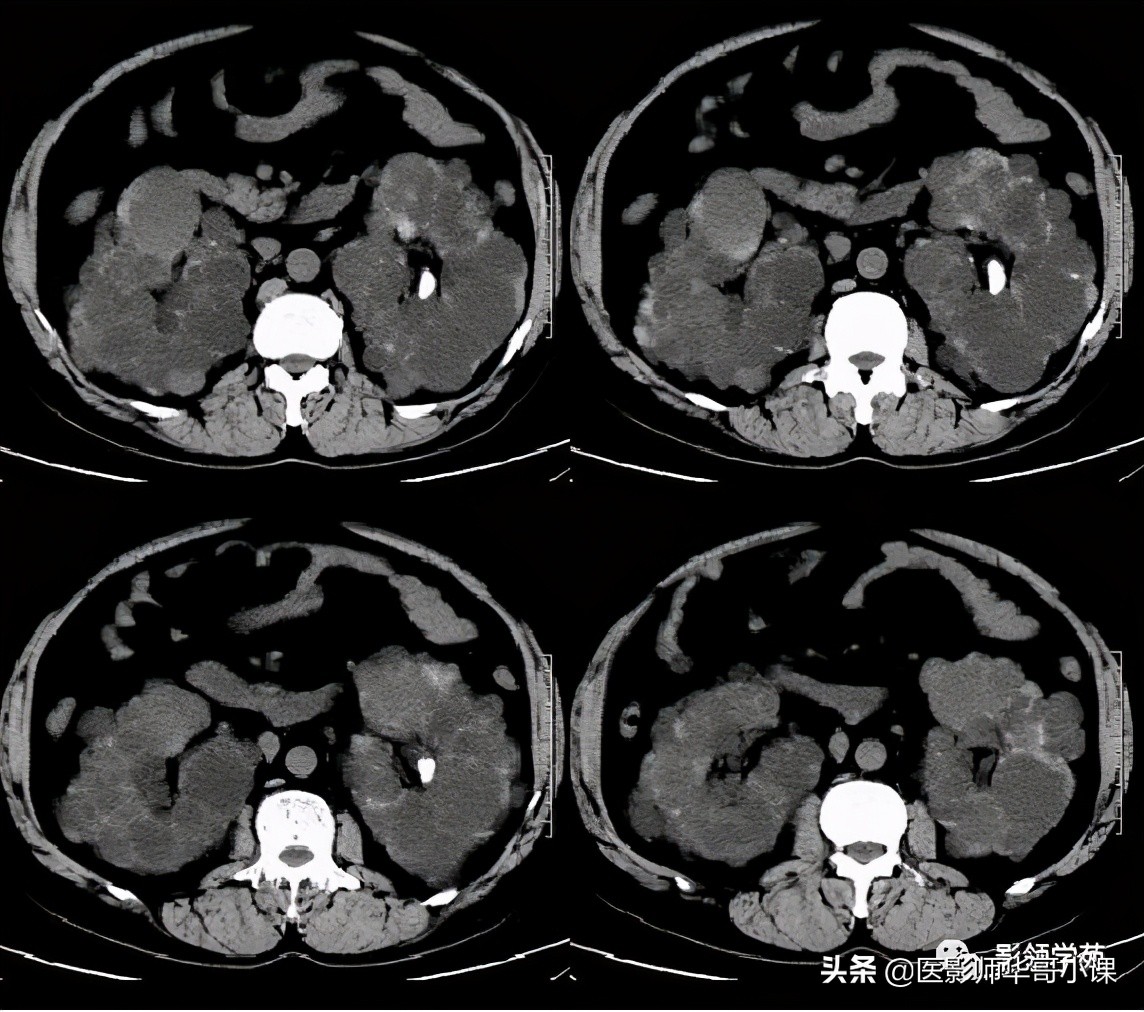

- 部分囊状扩张的胆管腔内有门静脉分支(箭头)

Caroli病影像诊断要点

1、肝内胆管不成比例的扩张,并与正常胆管相间,这是鉴别本病与继发性阻塞性肝内胆管扩张的关键所在,后者表现为从中央向末梢逐渐变细的、成比例的扩张。

2、“中心点征”是又一重要的征象,是指囊肿阴影内的小点状软组织影像,平扫密度等于或高肝实质,在T2WI序列上呈环状低黑信号,中央区呈圆柱稍高信号,其病理基础是门静脉分支被胆管扩张的囊壁包绕,并在切面上呈轴位投影。Seth等认为“中心点”征象的出现足准确的诊断本病。